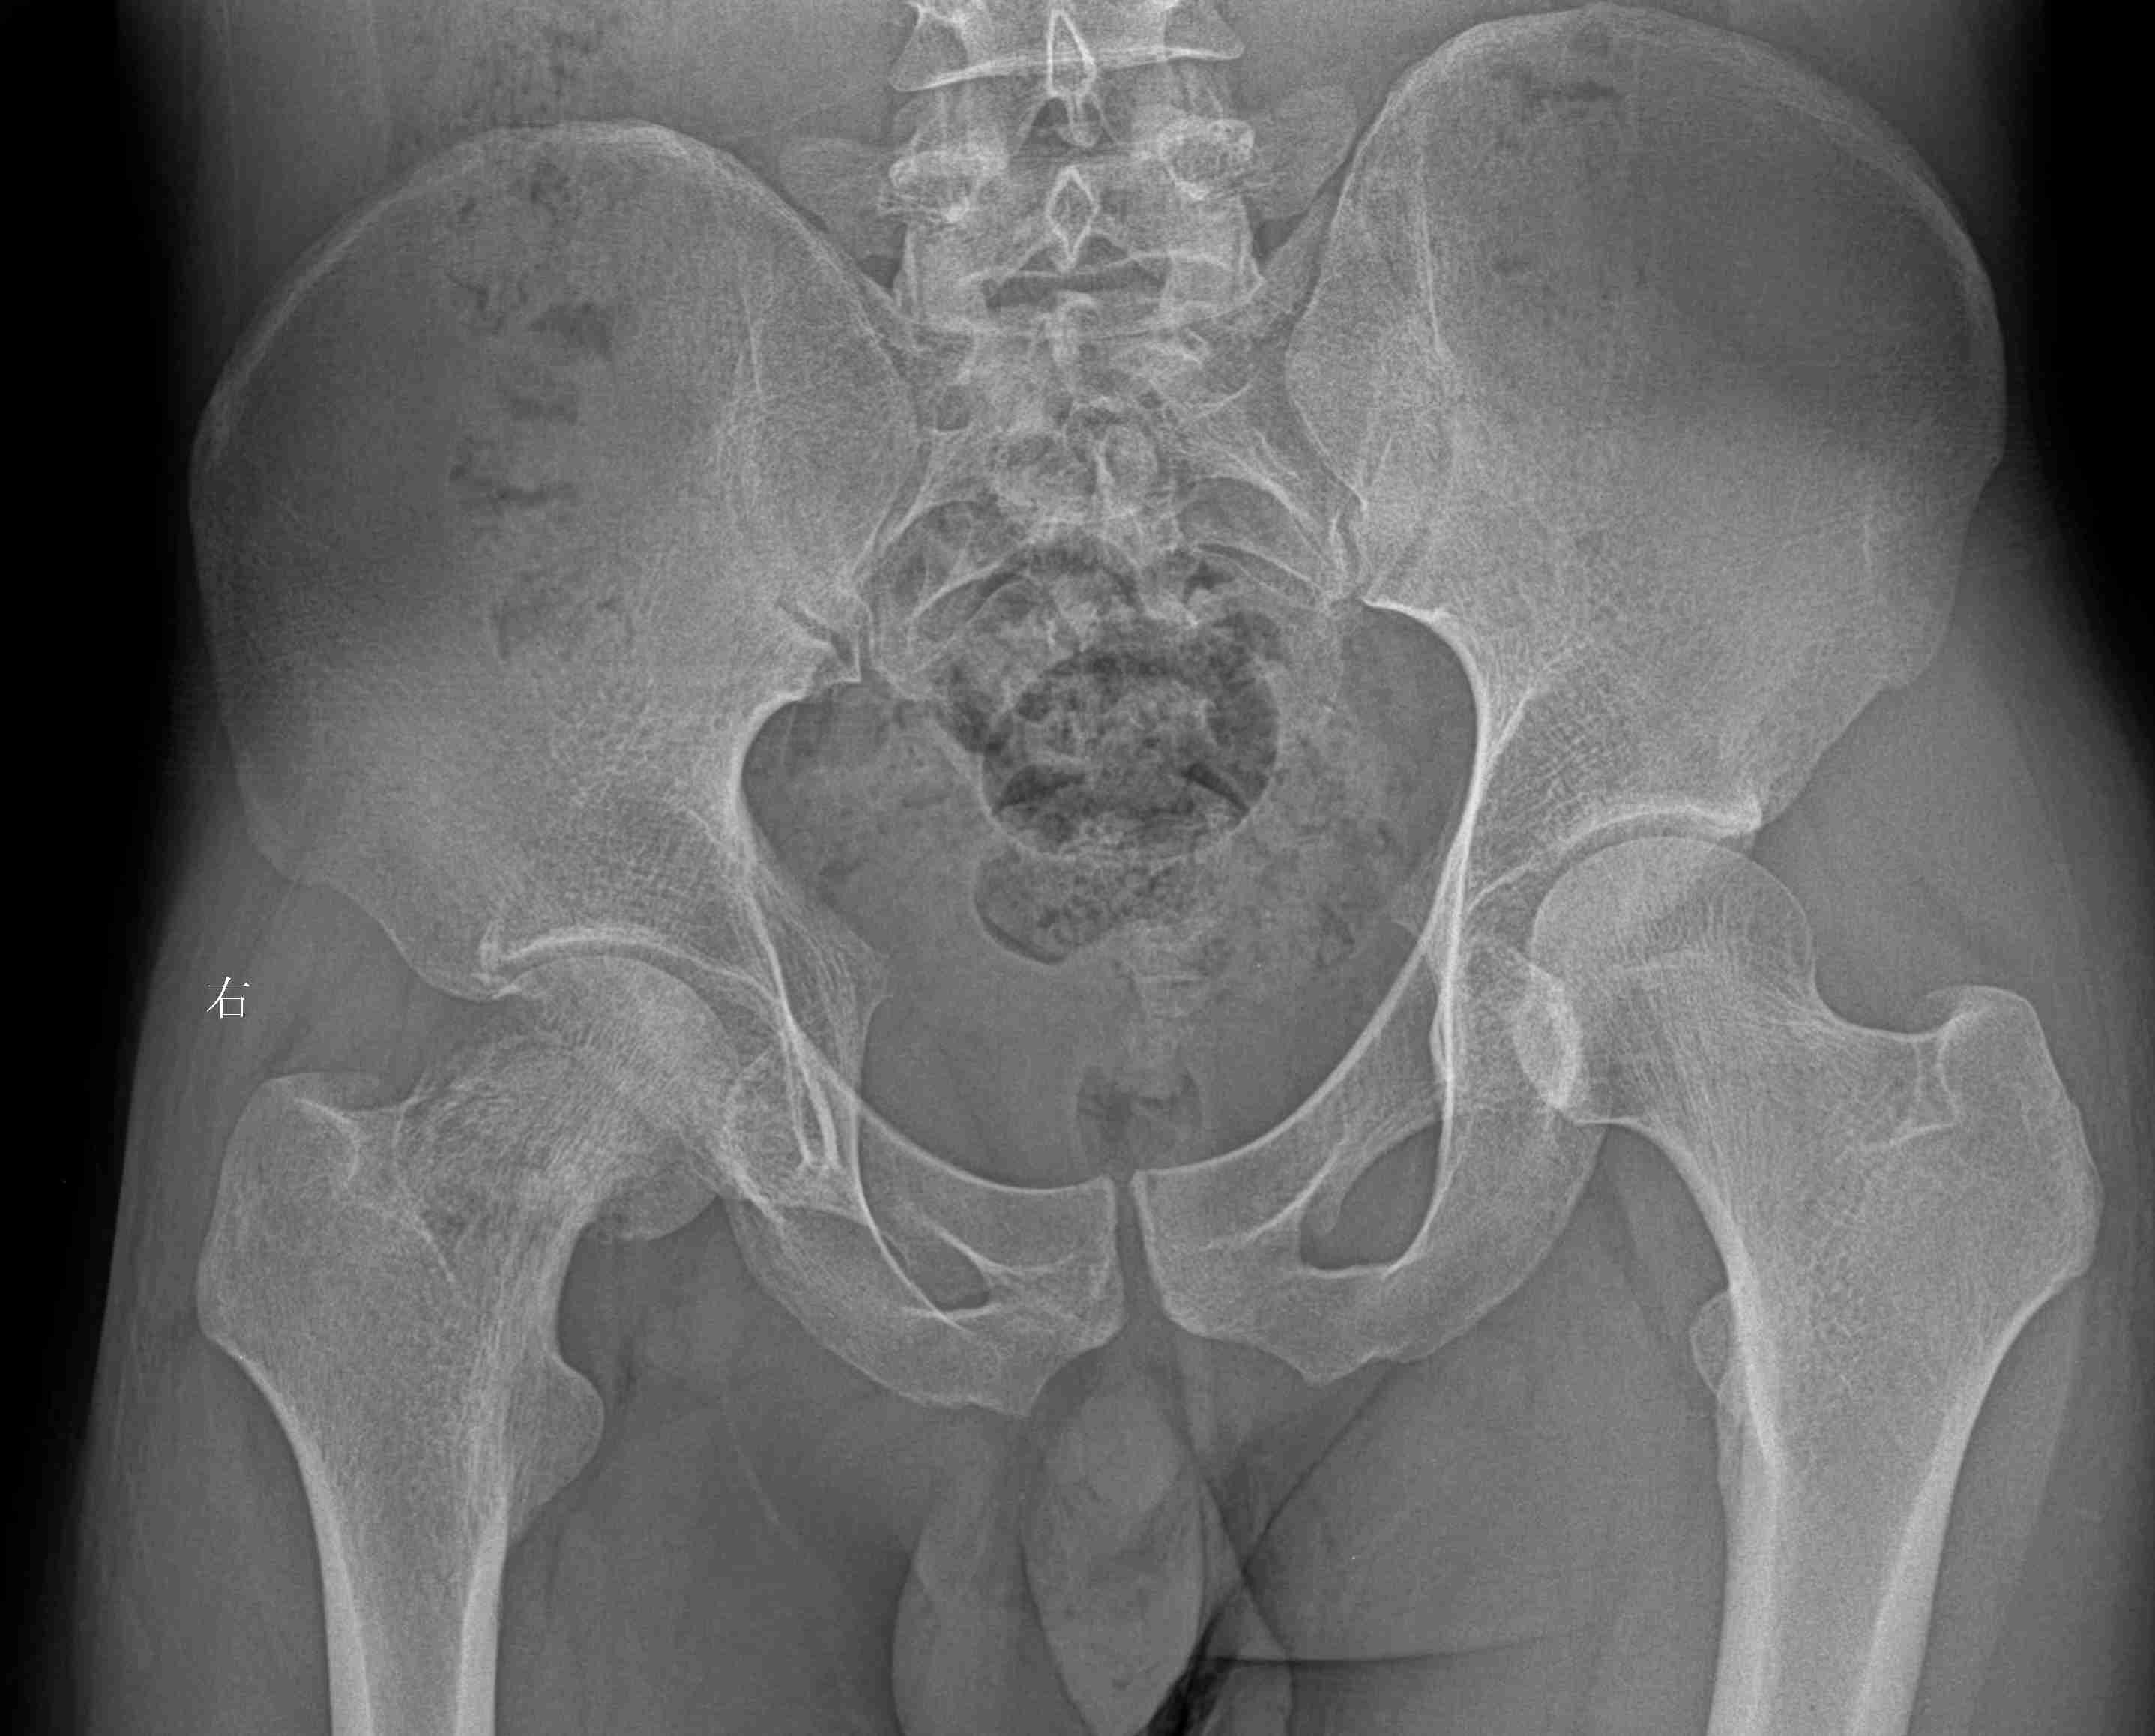

右侧股骨淋巴瘤

男,25岁,无明显原因出现右髋部疼痛3个月。体查无特殊。实验室检查正常。胸片、彩超均正常。

无意中看到的病例,较有难度,说3个诊断看看能否中的。

多数战友良恶性定性正确,少数战友完全与病理结果相符,结果

骨淋巴瘤